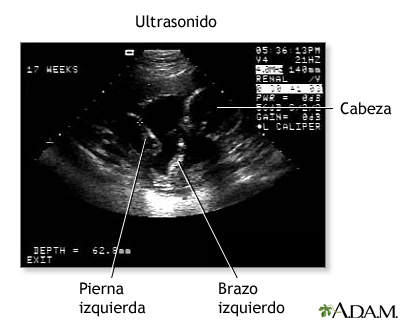

El ultrasonido es un procedimiento útil para monitorear el desarrollo del bebé en el útero. El ultrasonido se vale de ondas sonoras inaudibles para producir una imagen bidimensional del bebé dentro del útero materno. Las ondas sonoras rebotan en la estructuras sólidas del cuerpo y se transforman en una imagen en la pantalla del monitor. Las estructuras sólidas, como los huesos y los músculos, reflejan las ondas sonoras y aparecen de color gris claro o blanco. Las áreas suaves o huecas, como las cámaras del corazón, no reflejan las ondas sonoras y aparecen negras u oscuras. Un ultrasonido puede proporcionar información vital acerca del embarazo de la madre y la salud del bebé. Aunque no hay riesgos conocidos del ultrasonido por el momento, se recomienda mucho que las mujeres embarazadas consulten a su médico antes de someterse a este procedimiento.

- Estas ondas rebotan en las estructuras corporales, incluso el feto, para crear una imagen en el ecógrafo.